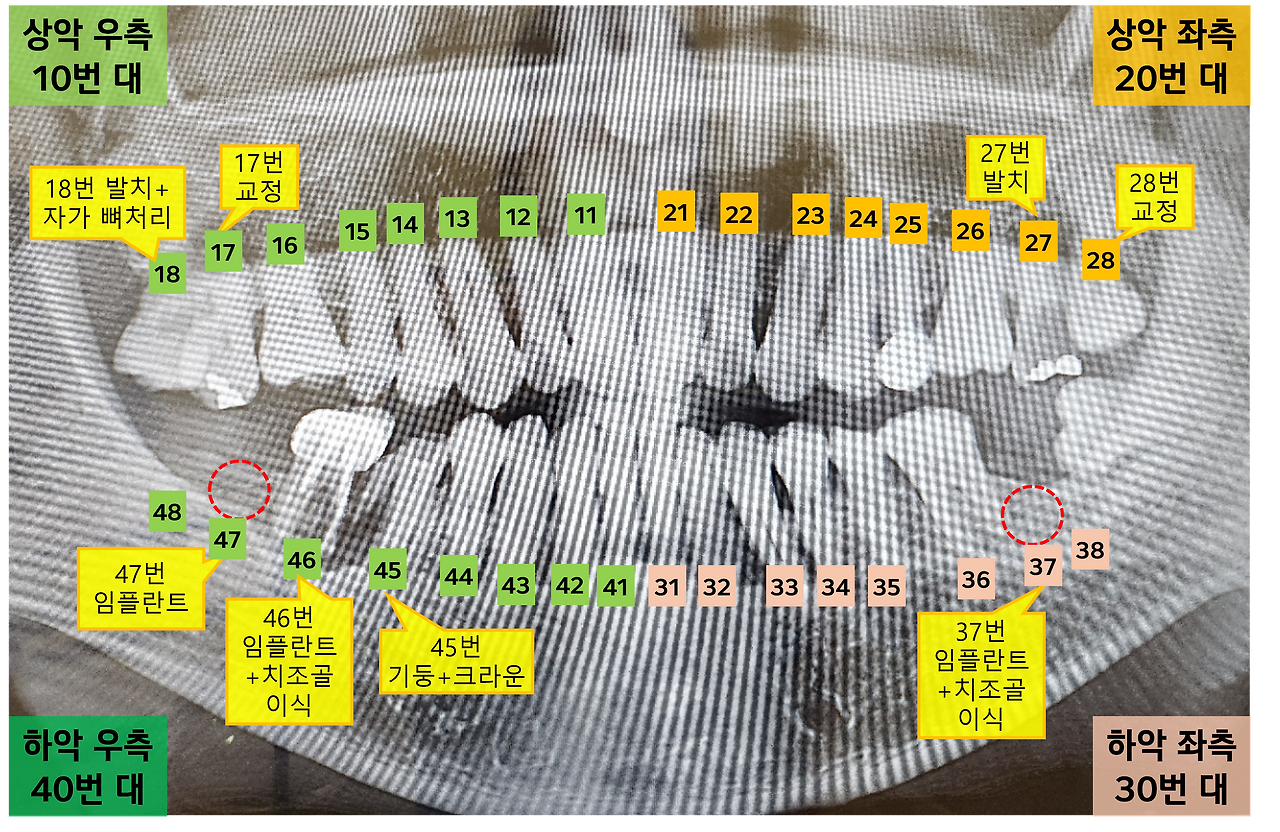

오늘 병원에서 제 파노라마 사진을 받아왔습니다. 그동안 다른 사람의 파노라마 사진을 보고 비교하다 보니 혼란스러운 부분도 있었고, 향후 치료 방법에 대해서도 한번 더 확인할 필요가 있다고 느꼈기 때문입니다. 직접 제 사진으로 확인해 보니 치아 상태가 꽤 안 좋아 보이기는 하네요.

치과치료_mine.png [제 파노라마 사진]

하지만 이 치아를 발치 후 임플란트를 하지는 않기로 했습니다. 대신, 인접한 26번과 28번 치아를 교정하여 빈 공간을 메우는 방식으로 치료를 진행하기로 했습니다. 은근히 치아 파노라마 사진을 자주 보다 보니 이제는 치료 방향이 조금씩 이해되기 시작하네요.

우선 27번을 발치한 후 26번과 28번 치아를 이용하여 간극을 메우는 방식으로 교정을 진행할 예정이라고 합니다. 그러기 위해서는 오늘 마취를 한 김에 26번 치아 쪽 잇몸뼈에 교정용 스크루를 박기로 했습니다. 전 처음에는 치아에 직접 스크루를 박는 줄 알았는데, 실제로는 잇몸뼈에 박는다고 하네요. 설명을 듣고 나니 좀 끔찍하다는 생각이 듭니다.